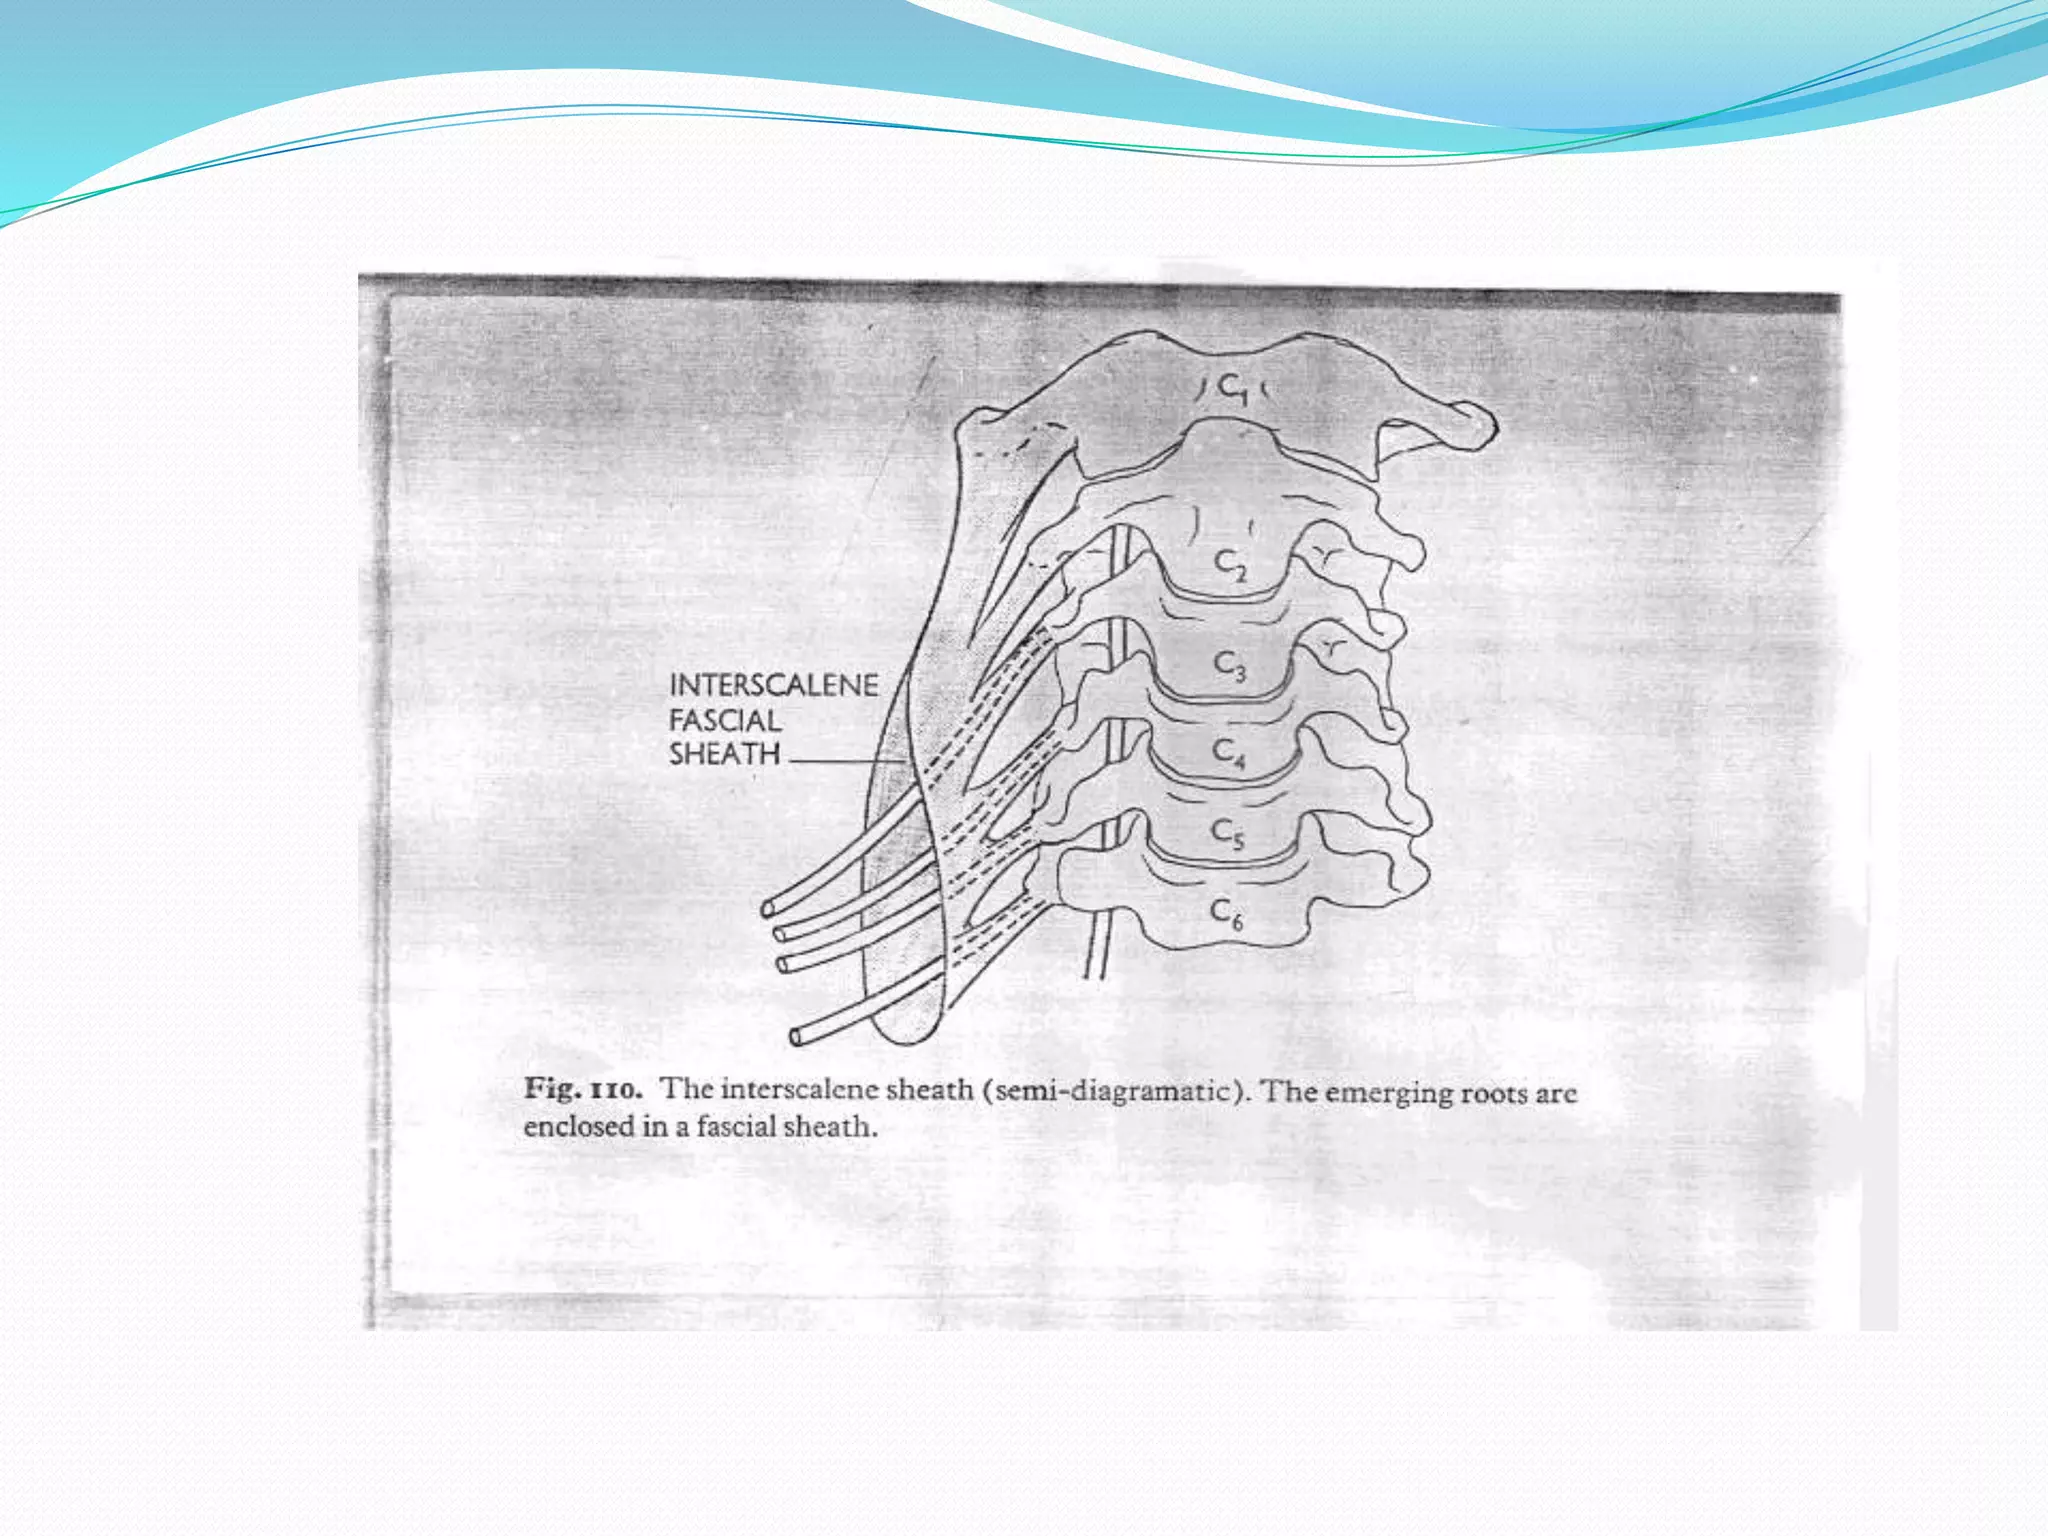

This document provides an overview of brachial plexus anatomy and techniques for brachial plexus nerve blocks. It begins with a description of the brachial plexus formation from cervical and thoracic nerve roots and its branching pattern. Four main approaches for brachial plexus nerve blocks are described: interscalene, supraclavicular, infraclavicular, and axillary. Details are provided on the anatomy and techniques for performing interscalene and supraclavicular brachial plexus blocks. Ultrasound guidance is discussed as an advancement which allows real-time visualization of needle and nerve. Complications are also summarized.